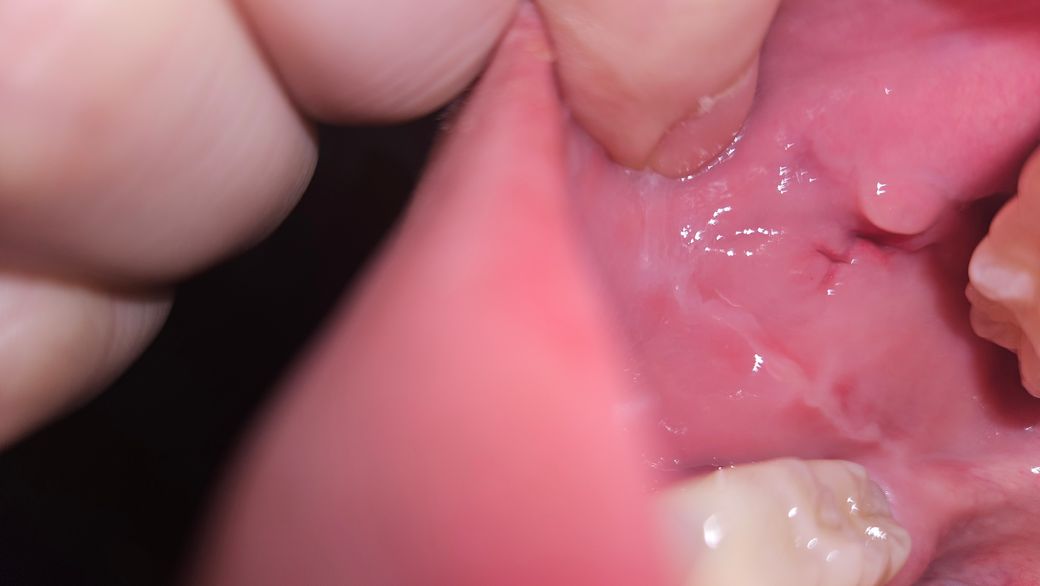

아무래도 불안한데 다시 안꼬매도 살이 차오르는거 맞나요?

볼 안쪽 점막 절개했고 봉합한 부위가

실밥은 일찍 떨어져 나갔는데

그에 비해 상처는

아직 벌어져있어요

사진에는 잘 안찍히지만 벌어진 공간이 꽤 되는데

재봉합 안해도 살이 잘 차오르는거 맞을까요?

잇몸아니고 볼 안쪽 점막입니다!

• 1번 째 사진